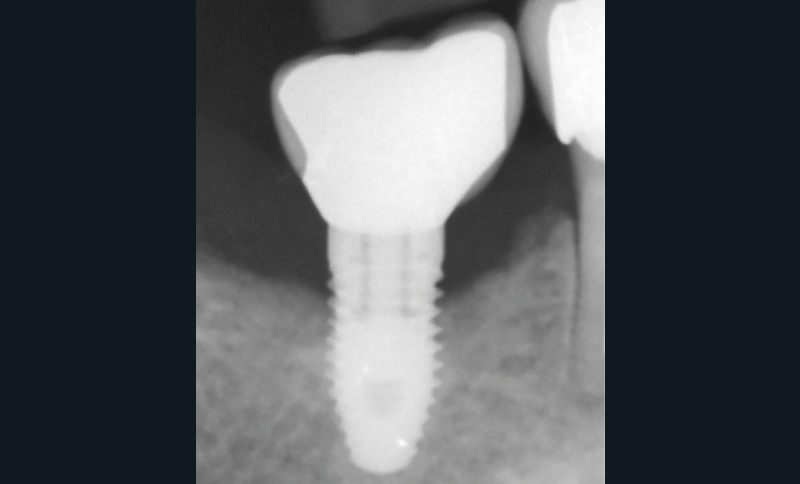

L’implant

- Péri-implantite sur l’implant 47, diagnostiquée en août 2022

- Poches de 6 à 7 mm

- Implant posé en 2017

- Nobel Replace Select RP (4,1 x 10 mm)

Dans les cas de traitement de péri-implantite, un suivi d’un an est considéré comme un suivi court. Néanmoins, le cas présent est stable après un an et ne présente aucun signe de récidive. Des contrôles supplémentaires sont nécessaires.